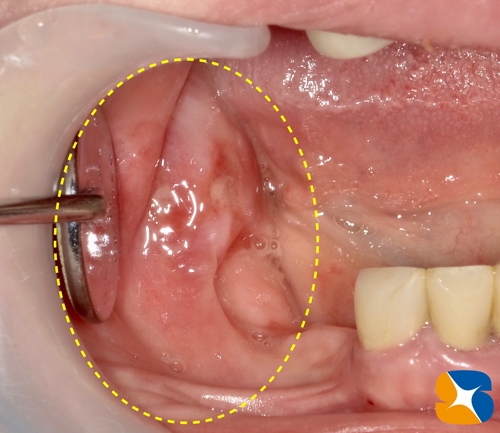

健康時とは一変、原形が分からない程大きく腫れ上がっています。ただし、見た目では親知らずの歯は確認出来ません。

切開すると、大量のクリーム状の膿汁が排出。それが落ちつきだした頃、親知らずの抜歯にとりかかりました。

歯茎の中からは、こげ茶色の歯石で覆われた親知らずの歯が出てきました。